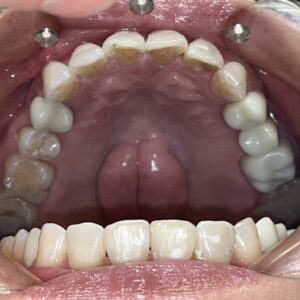

元々、上の前歯に入っている補綴物の状態がこちらです。

歯と歯茎の境が黒くなっているのがわかります。

まずは元々入っている補綴物を外し、仮の歯を入れていきます。

仮歯を入れた状態がこちらです。

そして前歯にフルジルコニアセラミッククラウンを入れた状態がこちらです。

Before After

歯と歯茎の境もなくしっかりとフィットし、綺麗な仕上がりになりました。

笑顔もとても素敵ですね♪